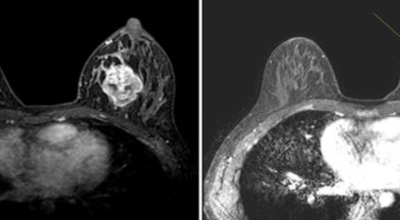

개인마다 초기증상은 다르게 나타날 수 있어요. 유방암은 우리나라 여성암 1위인만큼 많은 여성분들이 유방암에 대해 관심이 많아 검사를 많이 하는 추세입니다. 스트레스를 많이 받는 젊은 여성들도 유방 통증으로 진단을 받는 경우가 늘고 있다고 해요. 경우에 따라서는 유방암 초기증상이 없을 수도 있답니다. 유방암 자가검진 후 증상이 발견된다면 빨리 병원에 방문하는 편이 좋아요.

2. 유방암 초기증상 - 유방의 혹

보통 응어리가 잡히는 분들의 40%는 물혹으로 가벼운 질병으로 바로 치유가 되는 경우가 많은데요 20~30%의 확률로 유방암 초기증상일 가능성이 있다고 하죠. 따라서 매일같이 자신의 가슴을 마사지 해주시다 어느 날 응어리가 잡히게 된다면 유방암 검사 초기에 받아 보시기를 권해 드립니다.